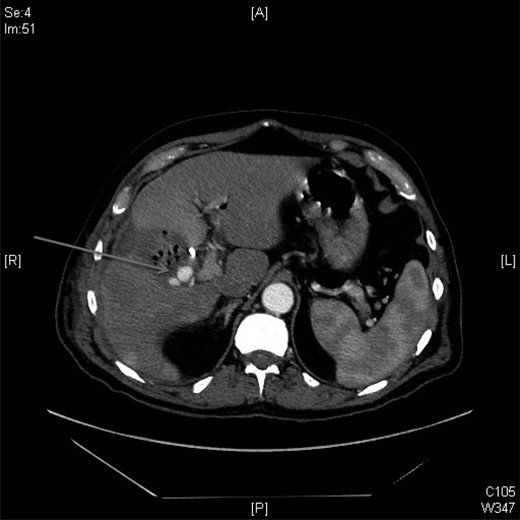

Upon presentation to our center, the patient was febrile (38.9°C) and complained of a left upper limb pain and swelling. The surgical drain was draining a mixture of bile and blood. His WBC count was 14 × 109/l, total bilirubin 35 µmol/l and the direct bilirubin 21 µmol/l. A duplex ultrasound of the upper limb revealed a left brachial vein thrombosis. Hematology was consulted, and a diagnosis of acute upper limb venous thrombosis was established. Owing to the presence of blood in the drain, he was kept on the maximum prophylactic dose of unfractionated heparin. A CT angiography of the abdomen showed two collections, one at the surgical bed near the drain, and the other was subcapsular below the left lateral lobe of the liver, as well as an aneurysm of the replaced right hepatic artery with an active bleeding blush (Fig. 1). The patient was immediately referred for an angiography, which confirmed the CT scan findings (Fig. 2). An arterial stent was inserted at the location of the aneurysm (Fig. 3), and a pigtail drain was inserted to drain any residual collection. An ERCP was also performed, which revealed a Strasberg Class D injury, and a plastic biliary stent was inserted. After the angio-stent insertion and stabilization of the patient, heparin infusion was started. Five days later he developed hematemesis and melena with a significant drop in his Hb to 2 g/l, and his total bilirubin became 183 μmol/l of which 91 μmol/l is direct. A gastroscopy was performed and showed hemobilia (bleeding from the ampulla of Vater). Subsequent angiography demonstrated a leak of contrast just above the arterial stent; hence, a further stent was placed to cover that area of the aneurysm. Similar symptoms reoccurred a week later, and a new angiography showed a new aneurysm from the left proper hepatic artery. A percutaneous thrombin injection of the aneurysm was performed as the bleeding branch was unreached via direct angiography and was filling in retrograde perfusion. During recovery a chest spiral CT was performed, which revealed the diagnosis of a bilateral segmental pulmonary embolism. Heparin infusion with low targets of partial thromboplastin time of 50–60 was started.

A CT scan showed replaced right HAP inside the collection (straight arrow).